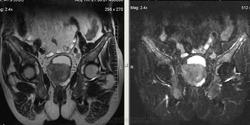

Метастазы рака простаты, кроме измений в позвонках видна сама первичная опухоль и лимфатические узлы (общий и наружный подвздошные слева, ещё один в левой подвздошной ямке).

После добавления томограмм исследования органов малого таза картина стала ещё печальнее...

Да, запустил пациент. До этого были проблемы с мочеиспусканием, рези, болезненность. Лечился самостоятельно от простатита, отмечал временное улучшение.